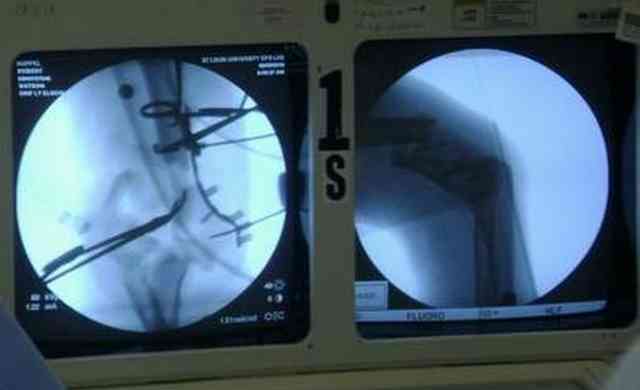

Впечатления об американской ортопедии. По проторенной коллегами дорожке в апреле по приглашению доктора Кульджанова Д., мы, 2 врача из казахстанской провинции -Канат Тезекбаев и Чертковер Григорий \ака Антон Андрианов\ провели 2 недели в университетской клинике города СентЛуис, Миссури. В прошлом году Никита Заднепровский, ранее побывав там, писал на форуме свои впечатления. Не желая повторяться, хочется довести до сведения коллег малую часть того, что нас поразило в США. Хотя одному из нас довелось поучиться три месяца в ФРГ по гранту АОАА и видеть клиники Швейцарии увиденное было ошеломляющим. Во-первых, подготовка врачей ортопедов длится 5-6 лет после колледжа, рабочая неделя их длится до 80 часов в неделю .Они –резиденты, закрывают все дежурства, прием пациентов. Опытные их учителя вызываются в ночное время по графику и очень многое резиденты делают сами под их контролем. Через пять лет к 33-35 годам он выходит самостоятельными врачами и ищут себе высокооплачиваемое место работы. Все стационары и амбулаторные приемы, частные или управляются частными компаниями, вся хирургическая служба высокодоходна и с врачами очень считаются, особенно по части приобретения заказанной ими техники. Экономическая целесообразность оставляет врачу только труд его квалификации, выписки, например, он диктует по телефону, мылом они летят в Индию, где дешевле труд машинистки, а к утру они уже в печатном виде у него в компьютере. Библиотека департамента ортопедии заставила утереть слезы доброй зависти, как и стопки журналов со всего мира на столе у профессора Кульджанова. Отсутствуют пленки рентгенограмм, доступ к сети с любого ПК, где хранятся все исследования пациента от поступления до амбулаторного этапа, интернет -до операционной. Удивительно крепок их командный дух, все дружно радуются быстро и удачно сделанной операции, бегут смотреть, что творится у коллеги, могут помыться на короткий момент для помощи и изучения, после идти продолжать свою работу. Еженедельные занятия с резидентами держат в информационном тонусе всех врачей. Можно много писать о работе приемного отделения, но те, кто видел сериал ER\Скорая помощь\ могут не сомневаться – на одного поступающего накидывается толпа врачей и персонала, а количество снимков и сканов МРТ и КТ не укладывается в наших головах. Правда о фильме они отзываются с иронией- фикшн, любовь на работе не крутим! Непререкаемый авторитет в клинике нашего куратора Джолдаса Кульджанова позволил нам свободно перемещаться по оперблоку и снимать операции. Активная хирургическая тактика при лечении политравмы, а именно таков состав пациентов, операции на нескольких сегментах позволяют избежать осложнений даже у престарелых . Так с д-ром Кулиджановым мы приняли участие в остеосинтезе перелома шейки, тибиального плато и предплечья у 92-летней дамы с протезом клапана, живущей на антикоагулянтах непрямого действия. Для выполнения операции анестезиологами путем переливания свежей крои и плазмы было создана на пару часов окно и операция была практически сухой. Вообще анестезиологи не выпячивают свою роль и с пониманием относятся к задачам ортопедов, вспоминается перл Илизарова- не больной для анестезиолога, а врач для больного\1982 год Курган\. Очень понравилась великолепная хирургическая техника всех докторов, крайне бережное отношение к тканями, практически не видели работы распаторами, минимально оголяется кость, используется инструментарий ЛОР и нейрохирургов. Орошение ран, джет- лаваж инфицированных ран проводится только физ.раствором. Многолетние наблюдения доказали состоятельность и даже к перекиси относятся критично -жжет ткани. ЭОП светит постоянно, даже измерение длины винта контролируется визуально, в их лексиконе нет слова СОЙДЕТ!Нет слов благодарности для Джолдаса, который опекал нас, как неразумных птенцов, часами сидел с нами перед монитором, ломая наши установки и пробивая косность совкового мышления. Те, кто уже бывал у него в гостях запомнили удивительный симбиоз полного западника с широкой восточной душой. Прилагаю несколько примеров изящной работы ортопедов из СентЛуиса.В первом случае у политравмированного пациента под ЭОП динамической пробой верифицирован разрыв МБС и выполнена фиксация позиционными винтами, 3.5 кортикальными.Кстати метчика в работе мы не видели, все винты self taping.Во втором случае у пациента с открытым многооскольчатым переломом дистального плеча на 4 сутки выполнен остеосинтез. Обратите внимание =доступ без резекции олекранона,медленная и ювелирная работа нетипичным для нас инструментом закончена полным восстановлением анатомии локтевого сустава.В небольшой дефект залит БМП\OP-1 Stryker ,продукт роста клеток человека в генной модификации\. Для профилактики гетеротопической оссификации ряд врачей применяют облучение на 2-3 сутки .Предвижу реплики скептиков - нам бы их зарплаты и оснащение, мы бы! Но для начала нам бы их учителей, их командный дух и их разумных рациональных организаторов!